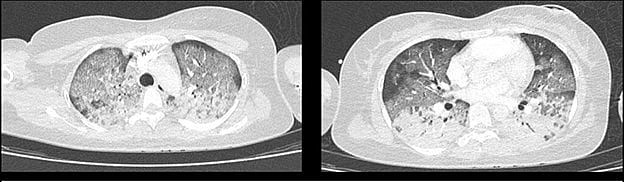

| Phổi bệnh nhân bị tổn thương được chụp cắt lớp vi tính. Ảnh BVCC |

Tại khoa Cấp cứu, các bác sĩ nhanh chóng thực hiện xét nghiệm sinh hóa và chẩn đoán hình ảnh. Bệnh nhân được xác định bị tổn thương đa cơ quan liên quan đến sốc phản vệ, trong đó tổn thương tim và phổi là nghiêm trọng nhất.